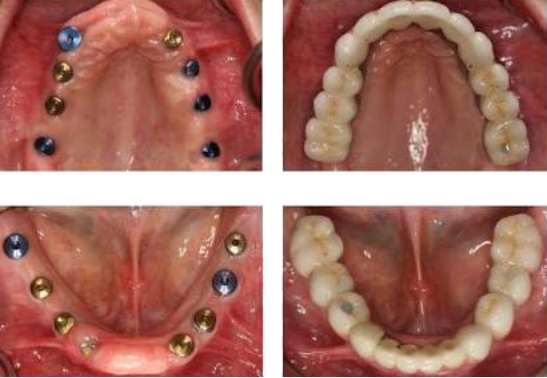

In the long term, implants are aesthetic, functional and comfortable. Gums and bone can recede around a fixed bridge or removable partial denture, leaving a visible defect. Resorbed bone beneath bridges or removable partial dentures can lead to a collapsed, unattractive smile. The cement holding bridges in place can wash out, allowing bacteria to decay teeth that anchor the bridge. In addition, removable partial dentures can move around in the mouth and reduce your ability to eat certain foods.